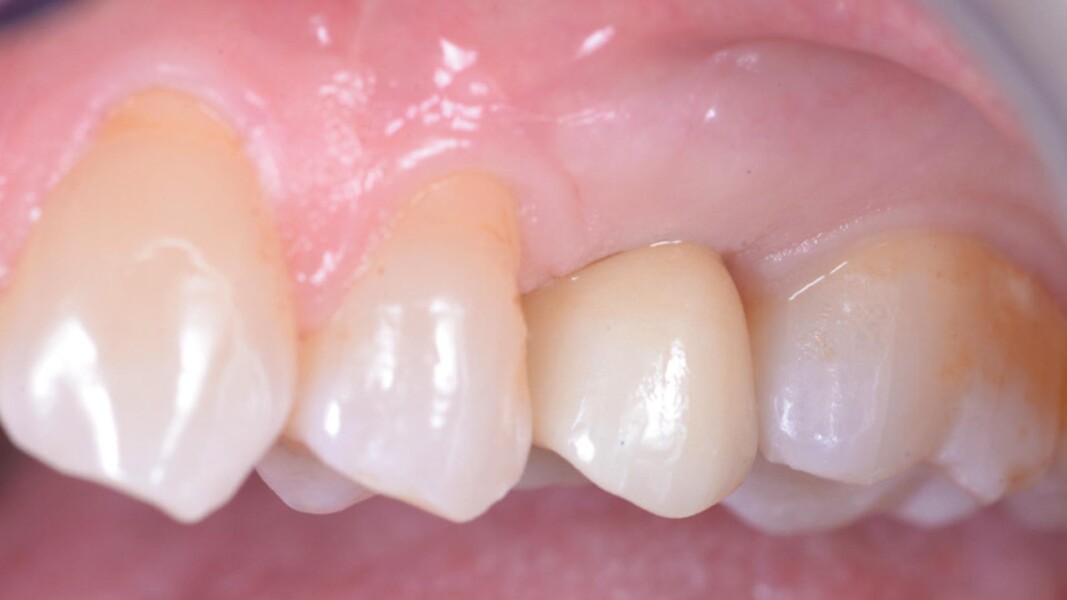

Una paziente di 50 anni presentava un premolare superiore non recuperabile. Dopo CBCT preoperatoria (T0) (Fig. 1), si è proceduto all’estrazione atraumatica e alla gestione dell’alveolo mediante posizionamento vestibolare di una membrana corticale eterologa (Lamina fine 0,7 mm, 35 × 15 mm, OsteoBiol) e riempimento con spugne di collagene (Figg. 2, 3). Sono stati applicati punti di sutura in nylon non riassorbibile 4/0. Dopo sei mesi di guarigione, una nuova CBCT (T1) ha consentito la valutazione della qualità ossea. Per la fase implantare è stato eseguito un lembo secondo la tecnica del roll flap, con preservazione delle papille interdentali e aumento del tessuto cheratinizzato (Fig. 4). È stato inserito un impianto JD Evolution Plus (4,3 × 11,5 mm) ottenendo un’eccellente stabilità primaria. Durante la chirurgia è stato prelevato un campione osseo per analisi istologica (Fig. 5).  Il lembo è stato suturato con nylon 4/0 intorno all’abutment di guarigione. Dopo due mesi, la paziente è stata riabilitata con una corona monolitica in zirconia realizzata da impronta digitale intraorale (Fig. 6).